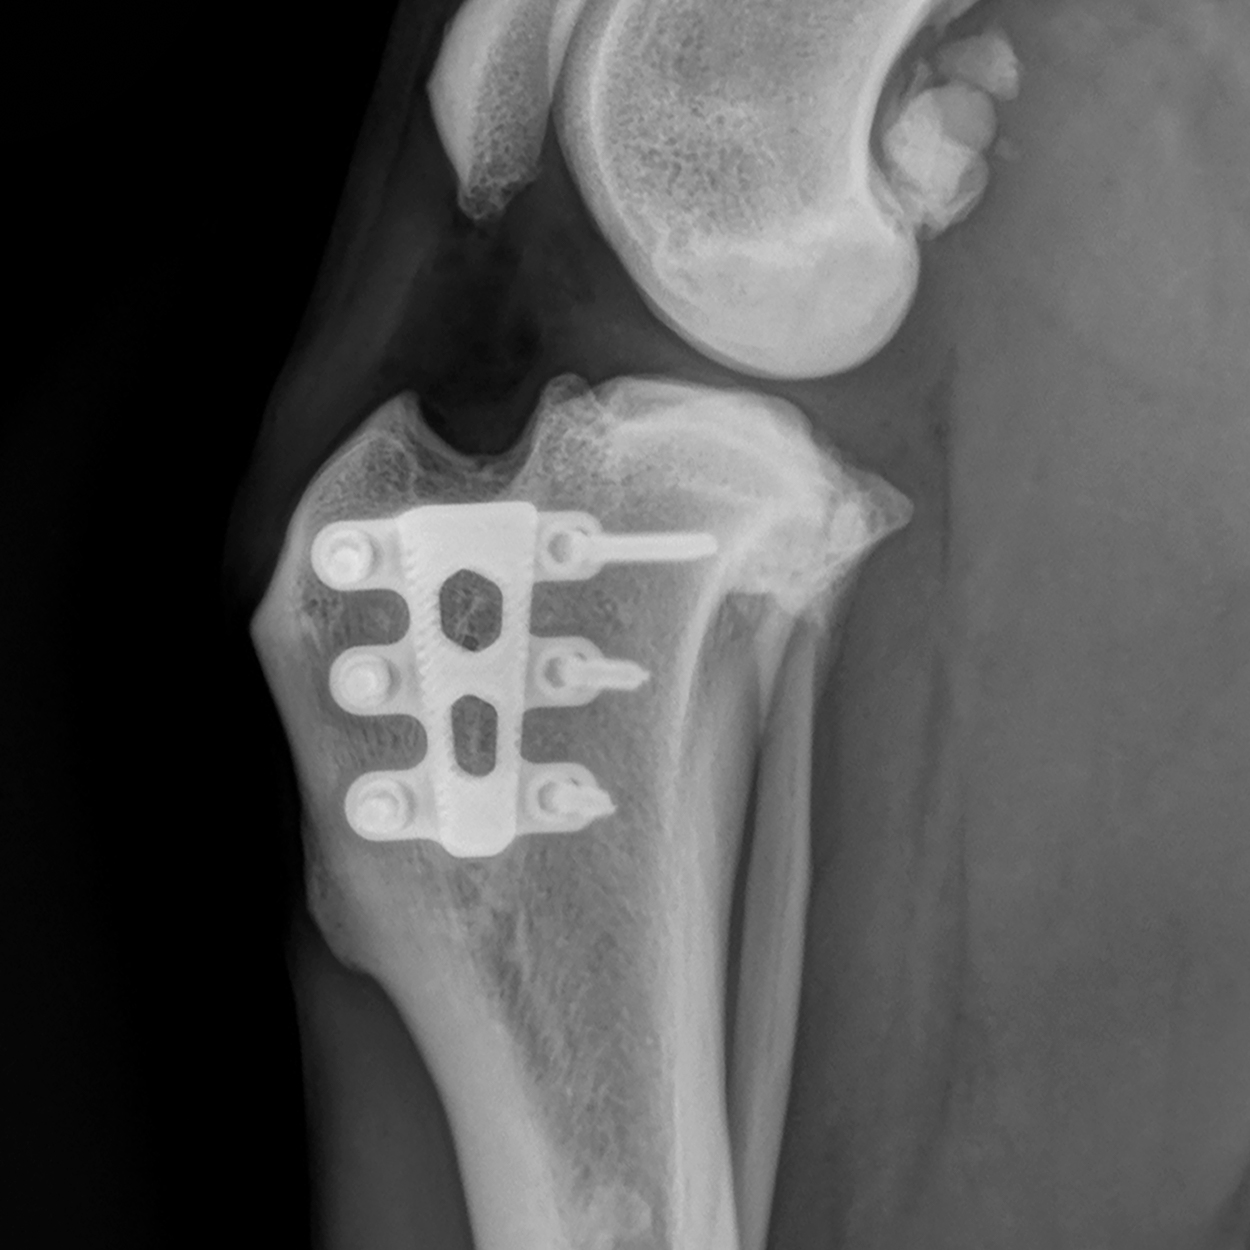

TTA RAPID ®

Now with 59 different cage sizes, TTA RAPID® is the most flexible surgical technique designed to repair a cruciate ligament injury. It allows for shorter surgery times, which means lower risk of infection and less costs.

TTA RAPID® & RAPID Patella Luxation